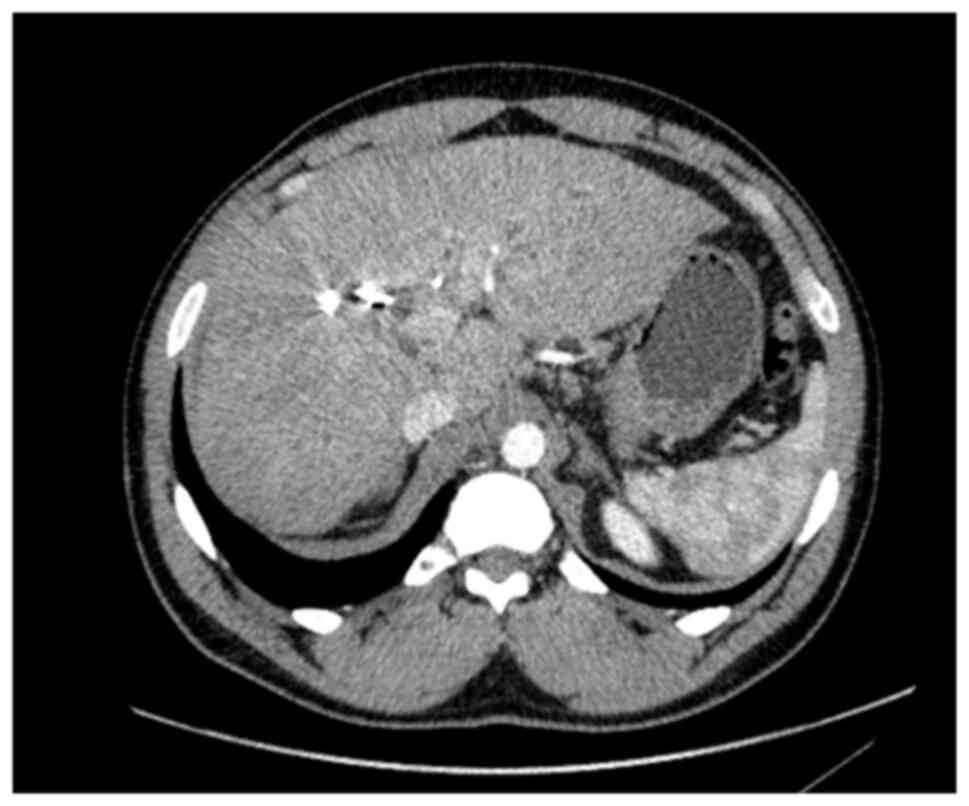

A 52-year-old male patient was diagnosed with PSC in 2015 at King s College Hospital (London, UK), confirmed by liver biopsy. He remained under regular surveillance by the hepatology team until April, 2017, when he presented with new-onset obstructive jaundice. Contrast-enhanced computed tomography (CT) revealed a hilar mass causing bilateral biliary dilation, and the working diagnosis was that of hCCA. After staging with fluorodeoxyglucose positron emission tomography (FDG-PET) and diagnostic laparoscopy, no evidence of metastatic disease was identified (Fig. 1). Portal vein embolization was performed to induce hypertrophy of the future liver remnant (FLR) in preparation for an extended right hepatectomy (ERH). Given the background of PSC, a 10-week interval was observed before repeat imaging, which demonstrated marginal FLR growth. The future liver remnant-to-body weight ratio (FLRBWR) was 0.42 at the time of surgery, corresponding to ~20% of total liver volume (Fig. 2).

Axial computed tomography image

demonstrating hypertrophy of the left lateral liver segment

following portal vein embolization, performed in preparation for an

extended right hepatectomy.

Figure 2

Axial computed tomography image demonstrating hypertrophy of the left lateral liver segment following portal vein embolization, performed in preparation for an extended right hepatectomy.